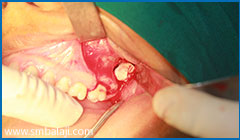

Surgical exposure of lower right impacted teeth

-

Surgical exposure of lower left impacted teeth